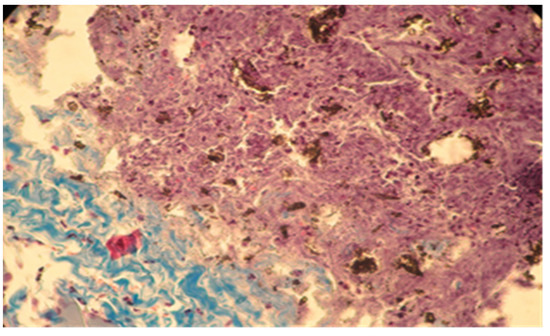

In group B, the local reaction was slightly reduced in intensity, with the necrotic area being much smaller compared to group A. The present cells, neutrophils, macrophages, and fibroblasts were fewer in number. The implanted material was partially reabsorbing, as shown by the migration of neutrophils and macrophages to the implantation site (Figure 7 and Figure 8).

Figure 8. Moderate necrosis area with pockets of implanted material and moderate leukocyte influx. Partial resorption of the implant material. Subcutaneous tissue, 7 days after implantation. Col. Trichrome Masson, ×200.